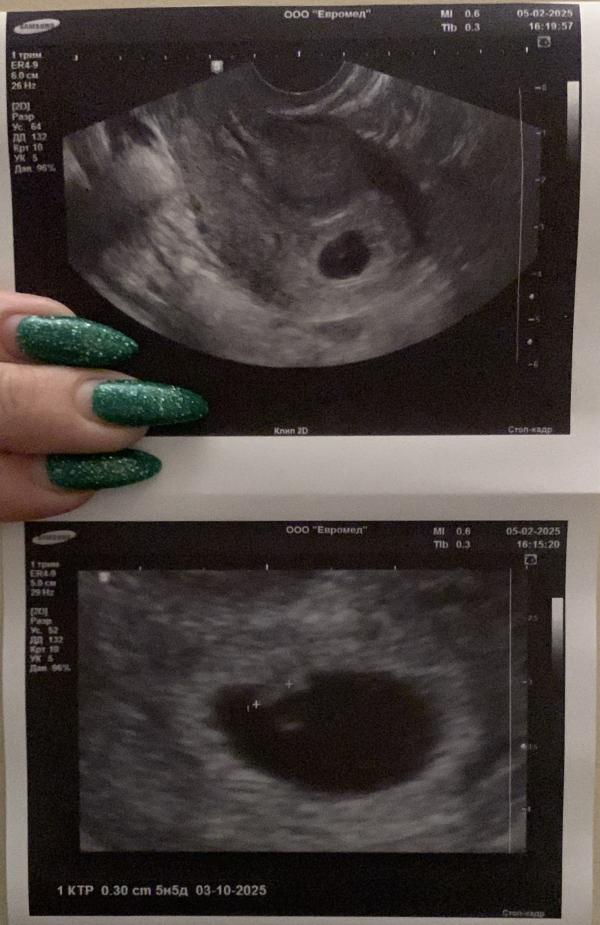

Первый осмотр 5.02.2025

ИТОГ:

5недель и 5дней❤️